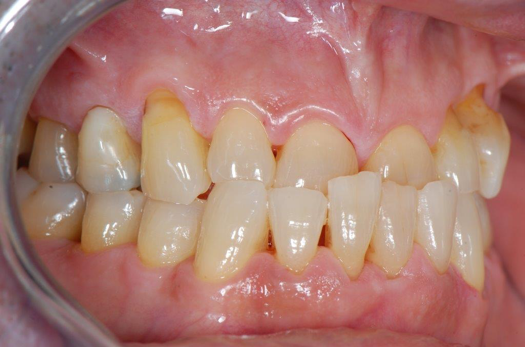

Fig 15. Provisionals 12 weeks postoperatively.

Figure 15

After the preparations were evaluated and accepted by the clinician, provisionals were completed with traditional crown-and-bridge techniques. Then the provisionals were fabricated with a replication stent derived from the diagnostic wax up (Figure 14). The provisionals were well-fitted to both the natural dentition and the ceramic dental implants (Figure 15). The provisional that was fixed to the implant was kept out of occlusion and had a narrow buccal-lingual occlusal table. The smaller occlusal table and short occlusal scheme provided light loading forces and stimulated the bone tissuethe brain detects the stimuli and sends osteoblasts to the area to increase bone density surrounding the implant. The recommendation for the light-loading provisional phase was to have the patient function with the provisionals for 4 weeks.